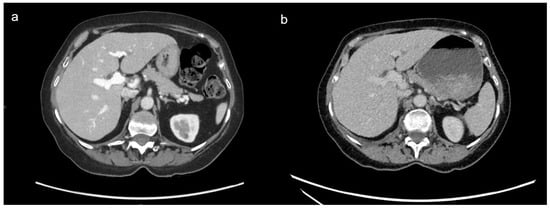

3.3. Comparison of DECT and SECT Results

3.3.1. DECT and SECT Comparison: Qualitative Results

3.3.2. DECT and SECT Comparison: Quantitative Analysis Results